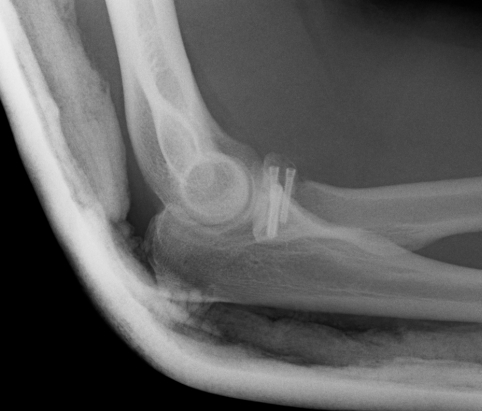

Overstuffing

| Lesser sigmoid notch | Symmetry of ulnohumeral joint |

|---|---|

|

Radial head shoulder articulate with lesser notch

Ensure no gapping of lateral ulnohumeral joint |

- cadaveric study

- increased medial ulno-humeral joint line gapping with overlengthening of 6 or 8 mm

- increased lateral ulno-humeral joint line gapping with overlengthening of 2 mm